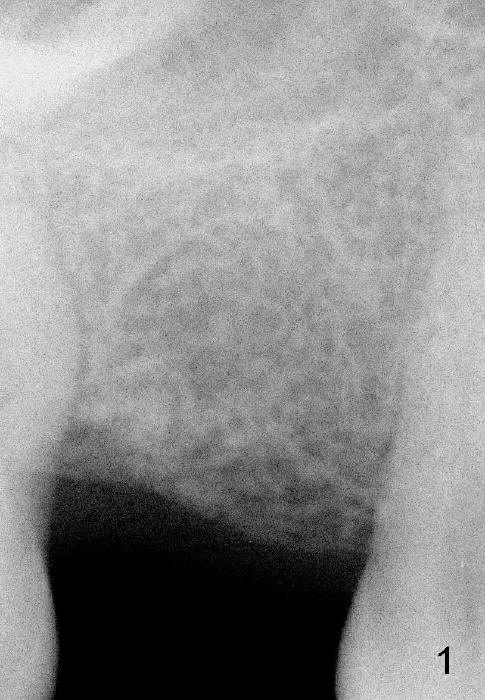

The bone density in the middle of the edentulous area is low (Fig.1 (PA taken immediately pre-implantation; 3.5 years post-extraction ), corresponding to the residual roots (Fig.1' (3 years prior to extraction). Bone expansion and condensation is necessary.